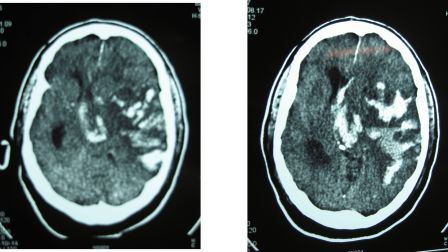

En este caso se trata de una hemorragia en el lugar de la isquemia cerebral en el territorio de la arteria cerebral media izquierda y en el contralateral:

En este caso se cree que además del tratamiento trombolítico, la causa de la hemorragia cerebral puede estar relacionada con una enfermedad subyacente como la angiopatía amiloide (en este caso no se llegó a realizar una RNM cerebral).